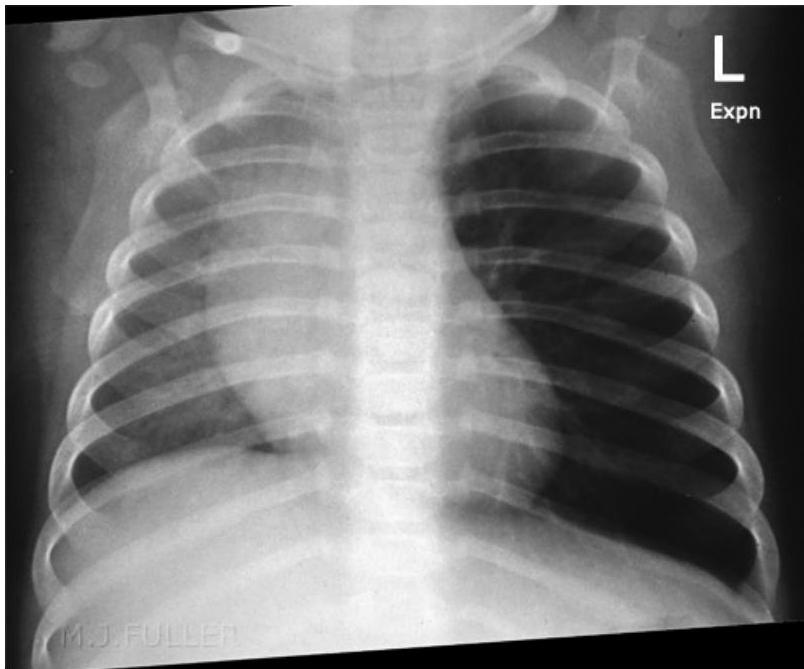

- Expiratory Chest X-ray or Fluoroscopy:

- Indicated for children with a suggestive presentation but normal inspiratory X-ray.

- On Inspiration: Lungs may appear similar as airways widen, allowing air past the FB.

- On Expiration: The FB can obstruct the bronchus as its diameter decreases. The greatest difference in lung aeration is seen here, as air is trapped in the affected lung while exhaled from the normal lung.